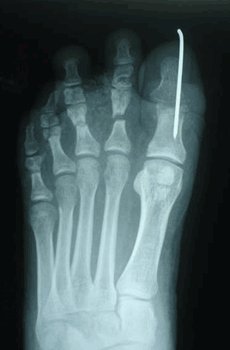

Caso 2: Hallux Valgus del Adolescente

Pie Izquierdo operado